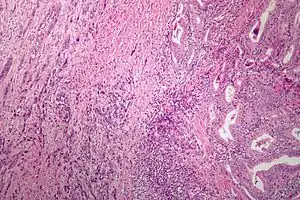

![]() Мікрофотознімок анапластичного раку щитоподібної залози. Фарбування ГЕ. Мікрофотознімок анапластичного раку щитоподібної залози. Фарбування ГЕ. | |